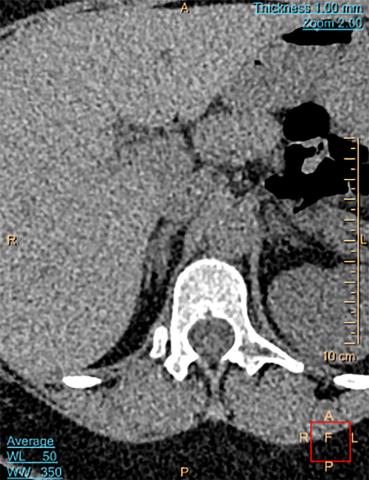

BI er en veldefineret tumor > 1 cm på den korteste akse på et aksialt snit [5] (Figur 1B) i en binyre af i øvrigt normalt udseende hos borgere uden aktiv kræftsygdom. En plump/hypertrofisk binyre er ikke patologisk. Binyren består klassisk af to ben (bredde 2-9 mm) og et korpus (bredde 4-15 mm) [6, 7] med en længde på 2-4 cm i aksialt plan. Binyrebarken producerer aldosteron, kortisol og adrenale androgener, mens binyremarven producerer adrenalin og noradrenalin. Patogenesen bag BI er omdiskuteret [8-11], og den genetiske og epigenetiske baggrund er kun begyndt at blive afdækket [12, 13] og er specielt uklar for ikkehormonproducerende BI.

Højresidig godartet binyretumor, homogen, velafgrænset, Hounsfieldenheder < 10, størrelse > 1 cm på den korteste akse.